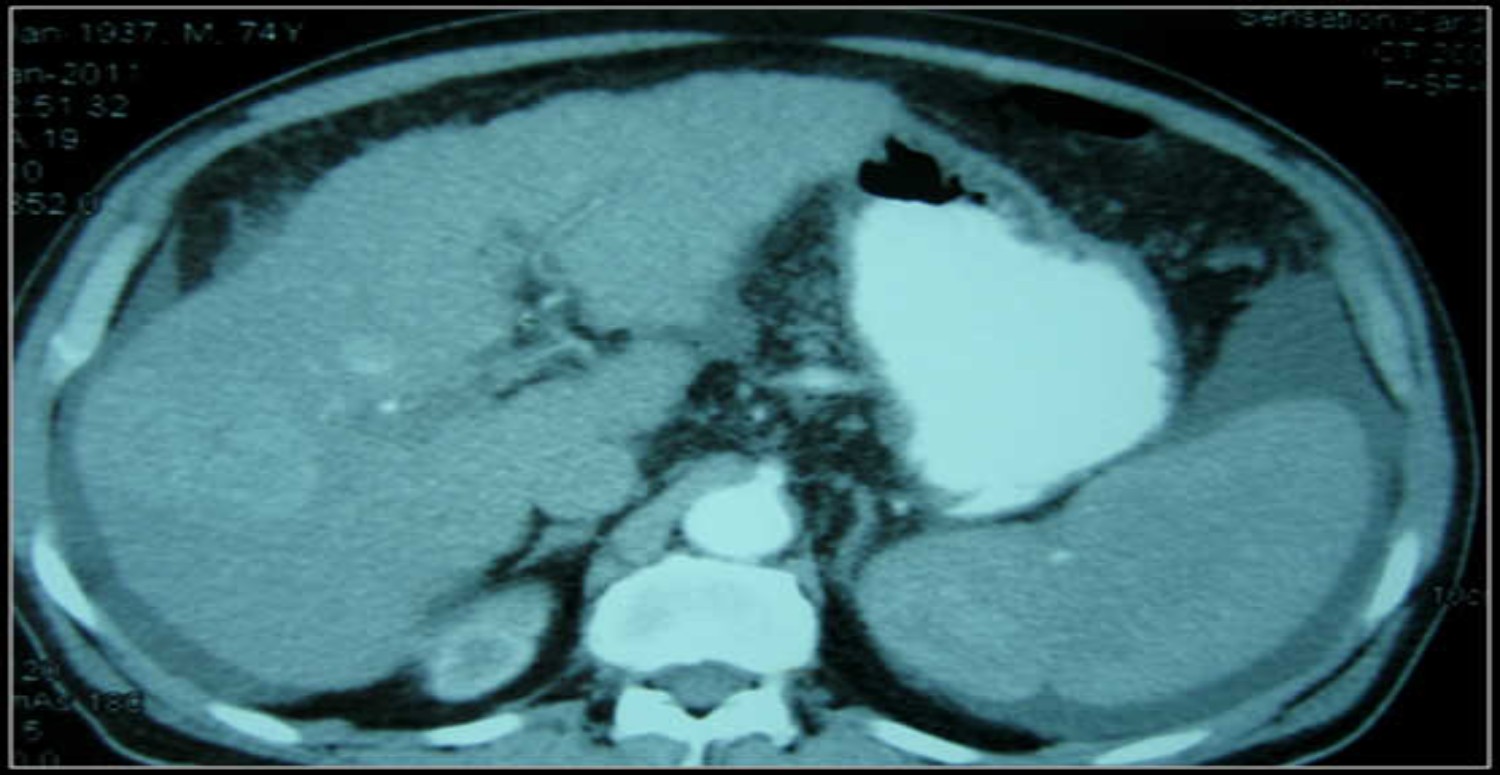

Karında sıvı birikmesinin tanısı, fizik muayene, kan testleri, karın ultrasonu, karın tomografisi, karın manyetik rezonans görüntüleme ve karın zarından sıvı örneği alınması gibi yöntemlerle konulabilir. Karında sıvı birikmesinin tanısı, altta yatan hastalığın tanısını da kolaylaştırabilir.